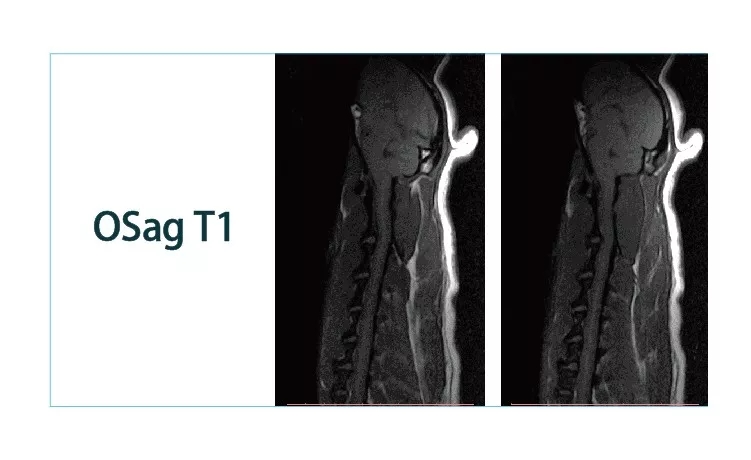

640.webp.jpg640.webp (1).jpg